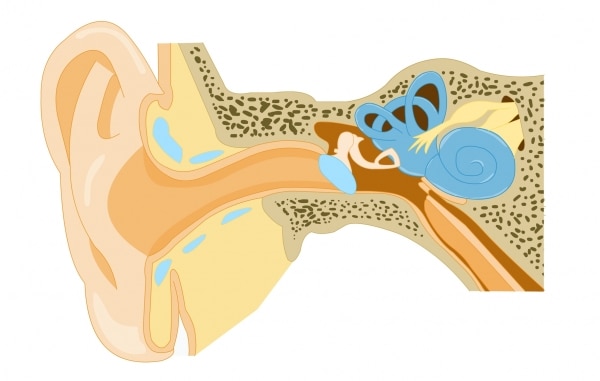

Si nous arrivons à percevoir ces sons, c’est grâce à nos oreilles, les organes de l’ouïe. Seule une petite partie est visible : l’oreille externe. Cachées à l’intérieur de notre tête se trouvent l’oreille moyenne et l’oreille interne.

Le pavillon de l’oreille externe, grâce à ses circonvolutions, capte les ondes sonores et les envoie dans le conduit auditif jusqu’au tympan, une membrane d’environ un centimètre, rigide et très sensible. Au contact de ces ondes, celui-ci se met à vibrer exactement comme le ferait la membrane d’un tambour. Le tympan transmet les vibrations vers les osselets de l’oreille moyenne : le marteau, l’enclume et l’étrier, qui ont pour rôle de les amplifier.

Le marteau, relié au tympan, se déplace latéralement lorsque ce dernier vibre. Le mouvement est alors transmis à l’enclume, puis à l’étrier. L’étrier est en contact avec la cochlée, cavité de l’oreille interne en forme de coquille d’escargot. Elle contient un liquide et les vibrations provoquent un déplacement de ce liquide. À ce stade, les ondes sont environ 20 fois plus fortes qu’au niveau du tympan. Dans la paroi interne de la cochlée se trouvent des cellules sensorielles. Celles-ci ont de petits cils qui baignent dans le liquide, comme des algues qui tapissent le fond de la mer. Les vagues dans le liquide inclinent les cils, ce qui déclenche des impulsions nerveuses qui partent vers le cerveau par le nerf auditif. C’est ce qu’on appelle la transduction.